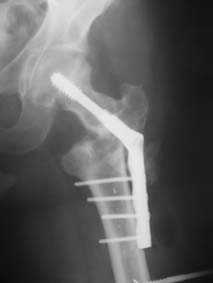

В этом случае, по-моему, аппаратный этап не был уж настолько важен. При использовании DHS или клинковой пластины при таком исходном положении отломков можно было делать и одномоментную коррекцию.

Срубить латеральную стенку периферического отломка для облегчения вальгизации.

В приложении пример пациента, близкого по картине к тому, что представил Виктор (варус и смещение периферического отломка на поперечник кзади). Сделали как раз то, что Виктор исходно намеревался - аппаратная коррекция и затем гамма.